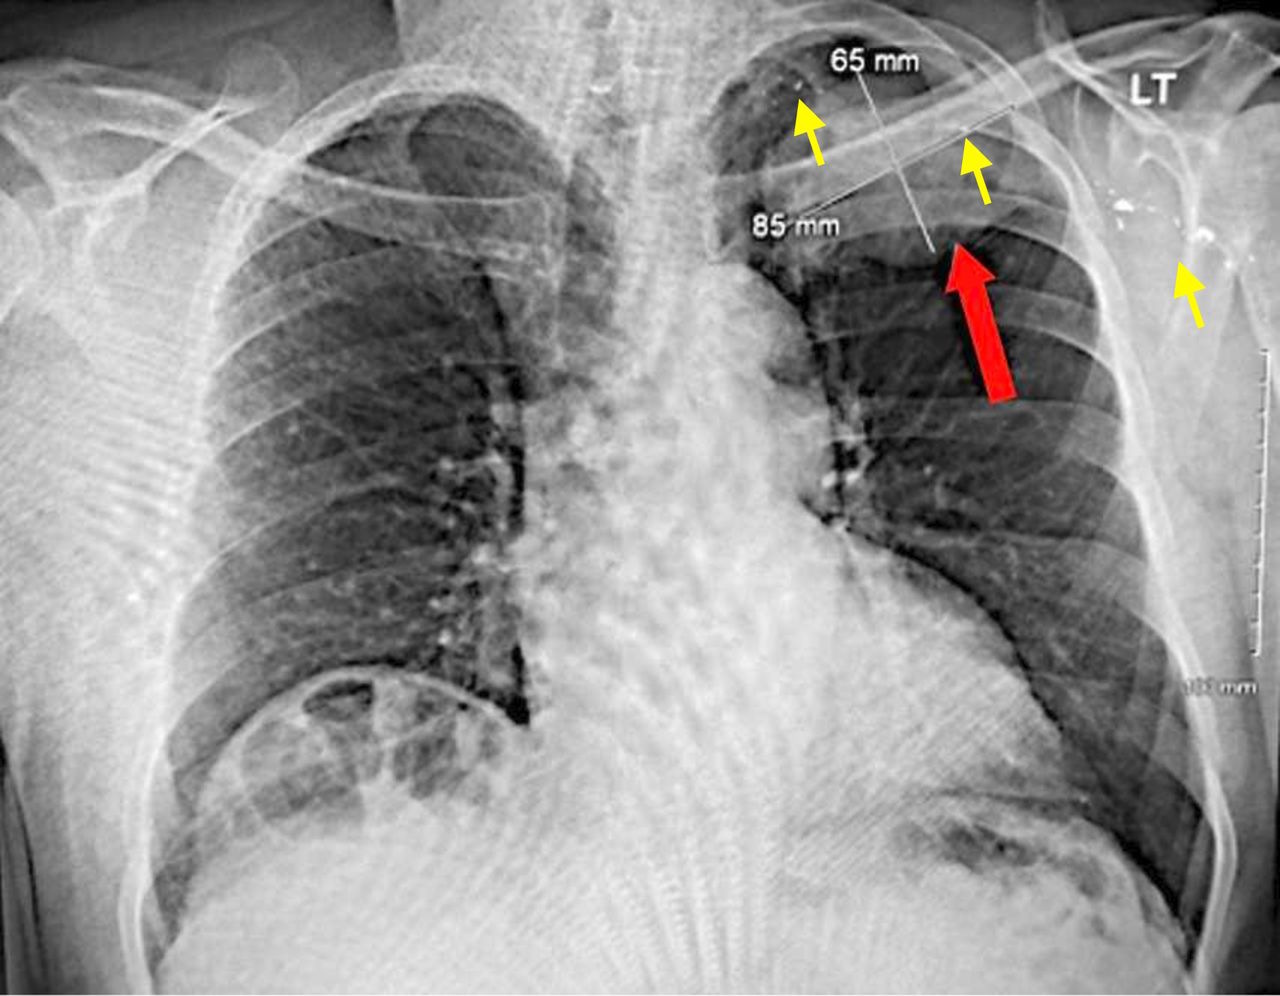

Рентгенівський знімок пухлини в легені (позначена червоною стрілкою) і фрагментів кулі (жовті стрілки). Bartholomew et al. / BMJ Case Reports, 2025

Пацієнт звернувся до лікарні через тривалий кашель і задишку, попри те, що до цього мав гарне здоров’я та самопочуття. Однак під час огляду в нього виявили пухлину розміром понад сім на сім сантиметрів, а також фрагменти кулі в пухлині, районі пахви та середостіння — простору між оболонками двох легень. Чоловік отримав кульове поранення під час виконання обов’язків, але тоді кулю не витягли, а пацієнта за місяць виписали додому.